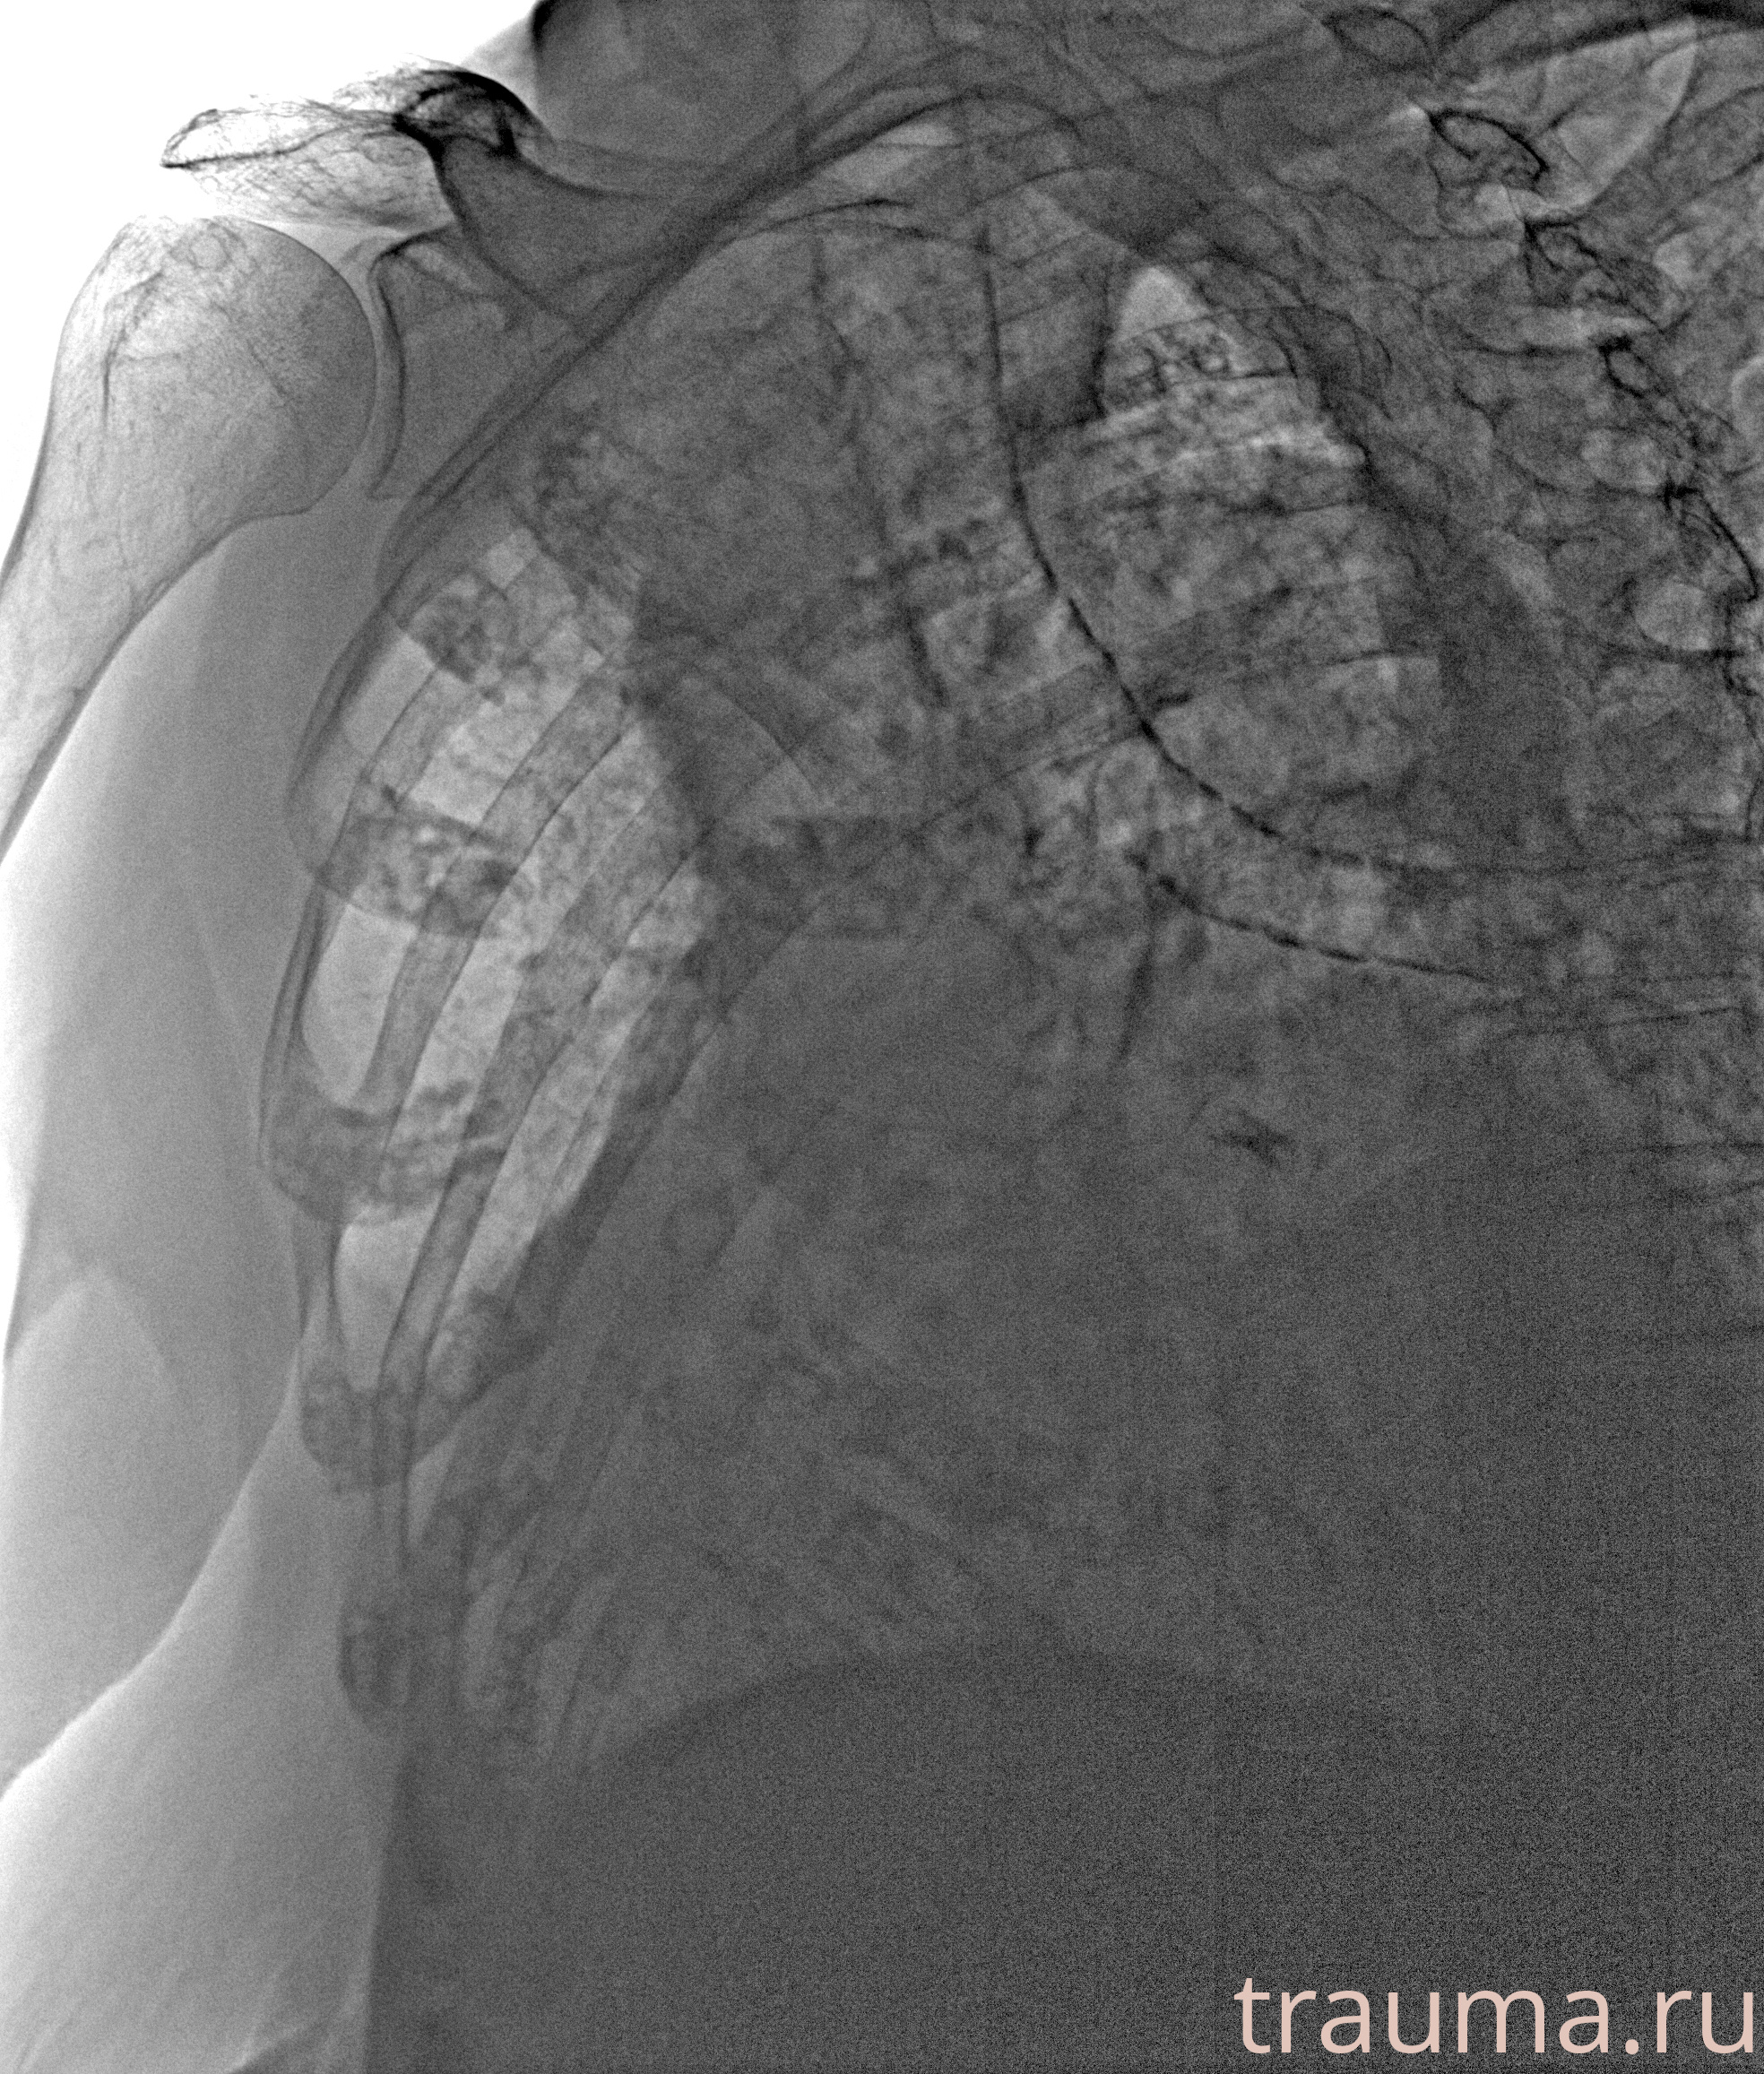

Рентгенограммы

Рентген на дому: по вашему адресу приезжает врач-рентгенолог, травматолог-ортопед с мобильным рентгеновским аппаратом, проводит диагностику травмы или заболевания, делает необходимые рентгенограммы, дает рекомендации по дальнейшему лечению. Получить качественные снимки в домашних условиях возможно благодаря уникальной методике, разработанной МосРентген Центром для института  Склифосовского